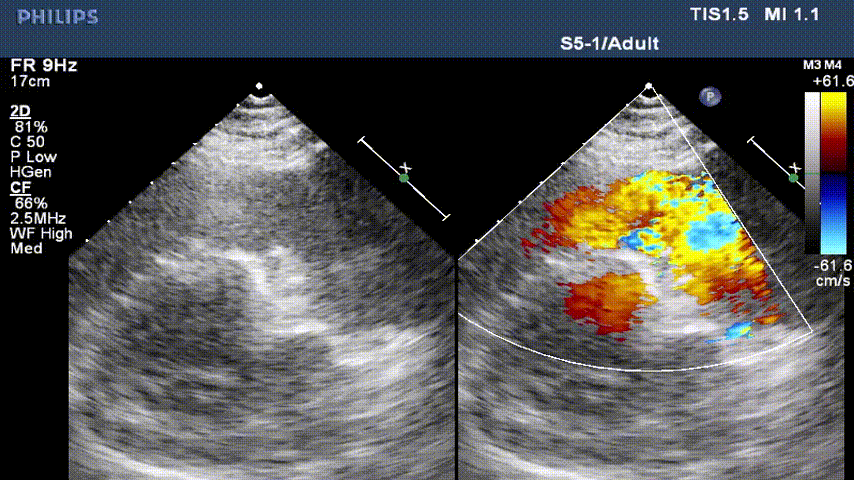

男性,45岁,法洛氏四联症术后35年,肺气肿病史,3年前行左肺肺结节切除术,患者6年前因体力下降,当地查出肺动脉瓣反流,未给予治疗。近2年来,活动耐量明显下降,步行数十米即感气喘,无法运动,体重增加后,活动耐量更差,入院前,患者自述“走几步路就觉气喘”。心超提示患者肺动脉瓣环内径约2.83cm,主肺动脉内经增宽,约4.61cm,频谱多普勒测及前向最大流速134cm/s,峰值压差7mmHg,舒张期探及大量反向血流信号(4+),瞬时量约17-21ml,三尖瓣轻度关闭不全,右房右室增大。

术前超声影像